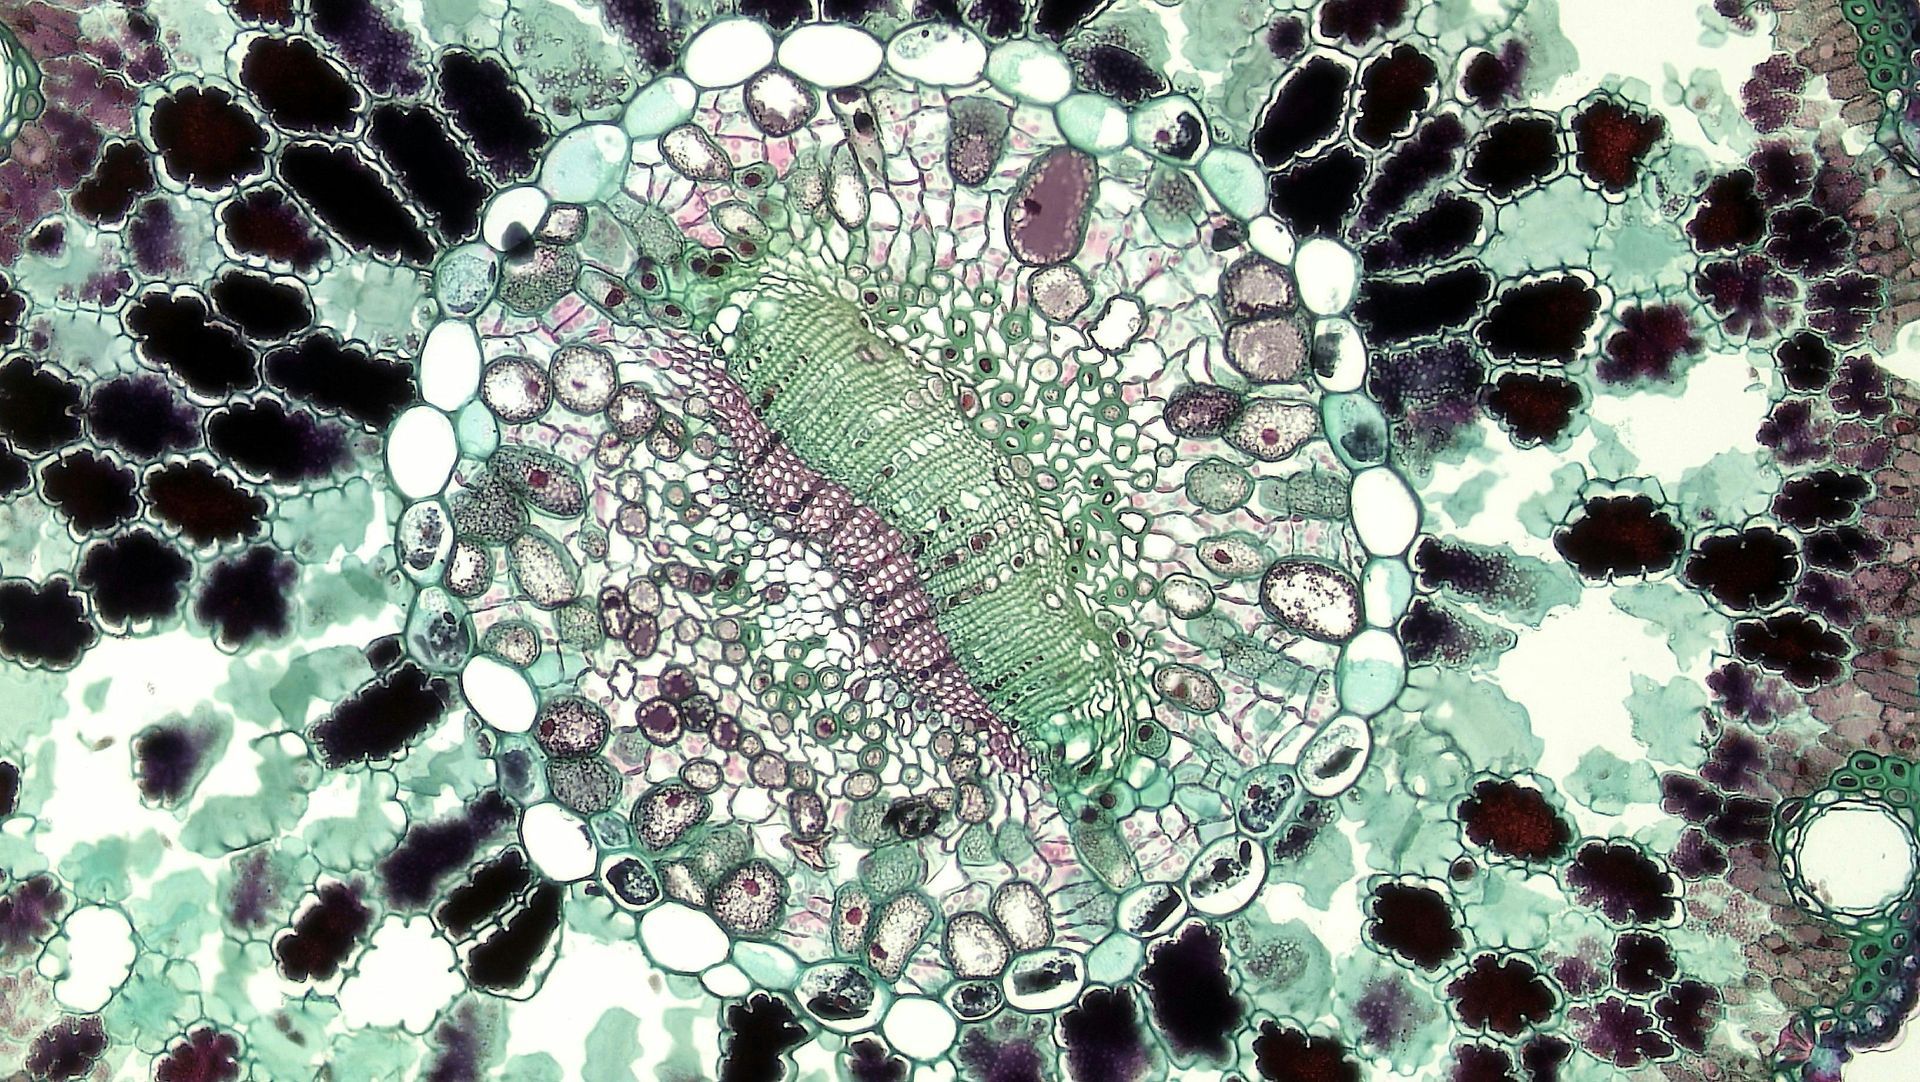

Vitamin B12- One of the Body's most important nutrient

Cells in a Microscope

By Polli Rayburn February 23, 2026

Boost natural energy with NAD+ IV therapy at Desert Elixirs in Terlingua. Support cellular function, metabolism & clarity. Book your wellness drip today.